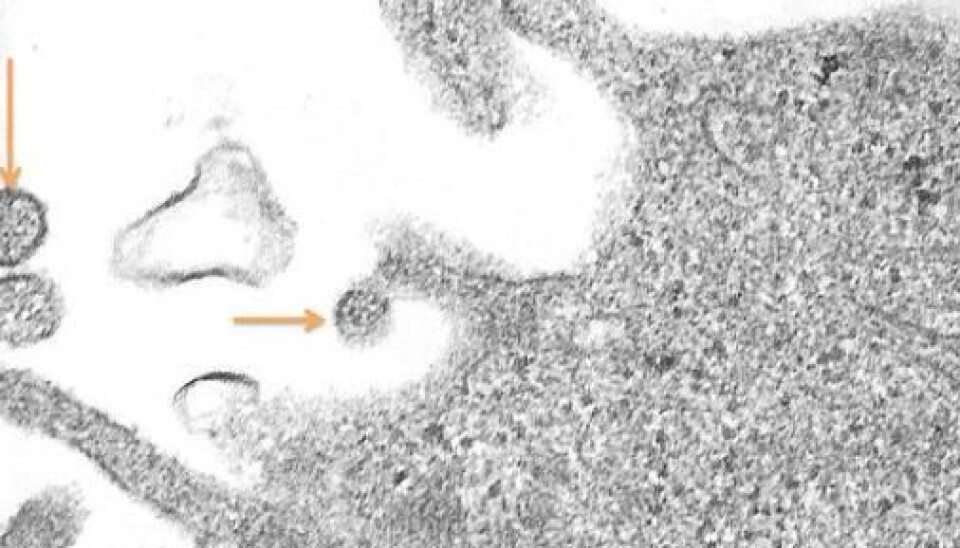

The human metapneumovirus (hMPV) under a microscope. The virus is spreading from an infected cell. (EM photo: Are Dalen)

The human metapneumovirus (hMPV) often appears disguised as a cold. Part of the reason it has stayed hidden from doctors is that it was only discovered in 2001. A team of Dutch virus researchers had the thrill of a lifetime when they realized that they had discovered a new virus. Their joy certainly wasn’t lessened by the fact that the virus they discovered turned out to be one of the most common viruses in children who are hospitalized due to respiratory complications.